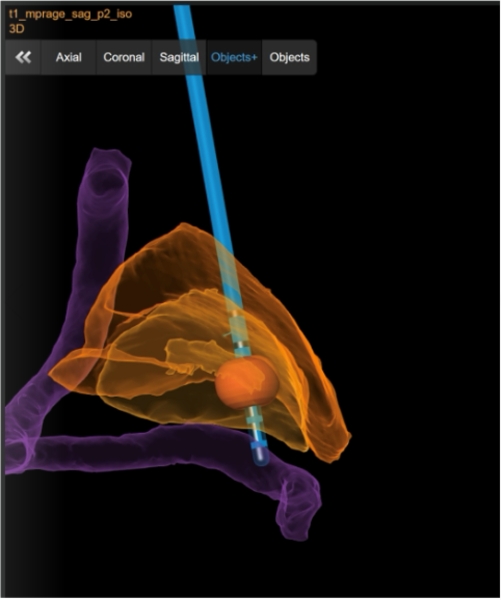

Tiefe Hirnstimulation

Bei bestimmten Bewegungsstörungen, die nicht oder nicht mehr ausreichend auf eine medikamentöse Therapie ansprechen, ist es möglich, die hierfür verantwortlichen Hirnareale durch die sog. Tiefe Hirnstimulation zu beeinflussen. Hierbei werden feine Elektroden in das Gehirn eingesetzt, um fehlerhafte Nervenstrukturen mit elektrischen Impulsen zu aktivieren oder zu hemmen. Beim Morbus Parkinson, dem essentiellen Tremor oder der Dystonie sind beispielsweise spezifische Hirnareale überaktiv, die dann gezielt durch die Tiefe Hirnstimulation gehemmt und die Symptome wie Zittern oder Muskelsteifigkeit dadurch unterdrückt werden können. Die Hirnregionen selbst bleiben dabei intakt, sodass die Stimulation jederzeit rückgängig gemacht werden kann. Die elektrische Stimulation wird durch einen Impulsgeber gesteuert, der ähnlich wie ein Herzschrittmacher unter die Haut an der Brust der Patient:innen implantiert wird. Die Einstellungen des Impulsgebers lassen sich von außen jederzeit verstellen, sodass die Stimulation an veränderte Bedürfnisse der Patient:innen stets angepasst werden kann.